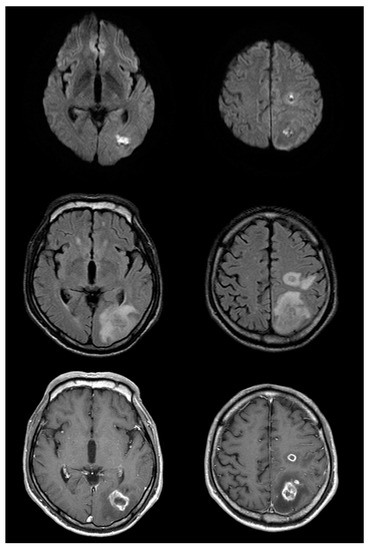

Figure 2.

Follow up brain magnetic resonance imaging on the eleventh day after symptom onset (top row: diffusion-weighted imaging (DWI); middle row: fluid-attenuated inversion recovery (FLAIR); bottom row: post-gadolinium). There is significant interval change with enlargement of the lesions on DWI and FLAIR images, as well as significant vasogenic edema. Post-gadolinium T1-weighted images show somewhat thick and irregular but complete ring enhancement.

Figure 3.

Magnetic resonance imaging (MRI) on the 52nd day after symptom onset reveals a decrease in the size of lesions compared with that in the prior study (top row: diffusion-weighted imaging (DWI); middle row: fluid-attenuated inversion recovery (FLAIR); bottom row: post-gadolinium). Edema and enhancement are markedly decreased compared to that in the previous MRI; changes originally seen on DWI are evolving and resolving as well.